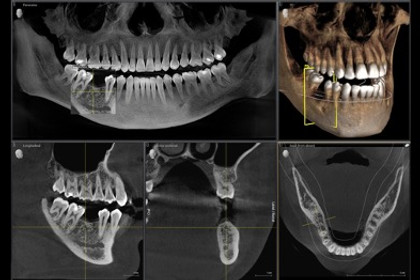

We use iTero Lumina and Primescan digital scanners to capture highly accurate 3D images of your teeth—without messy impressions